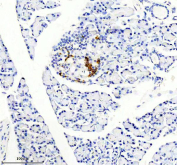

Somatostatin 28 Antibody. Immunohistochemistry analysis of formalin-fixed, paraffin-embedded rat pancreas tissue using a rabbit Somatostatin 28 antibody. Heat-induced antigen retrieval was performed in EDTA buffer at pH 8.0. The section was blocked with goat serum and incubated with primary antibody overnight at 4oC, followed by a peroxidase-conjugated goat anti-rabbit IgG secondary antibody. Cytoplasmic HRP-DAB brown staining is observed in pancreatic islet cells, consistent with Somatostatin 28 expression in endocrine cell populations within the pancreas.